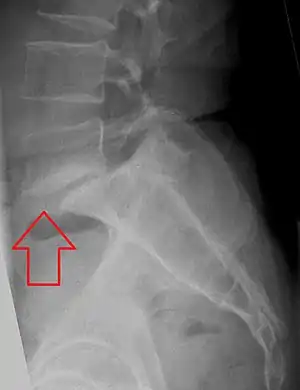

- L5 S1 Spondylolisthesis Grade II with forward slipping of L5 on S1 <50%